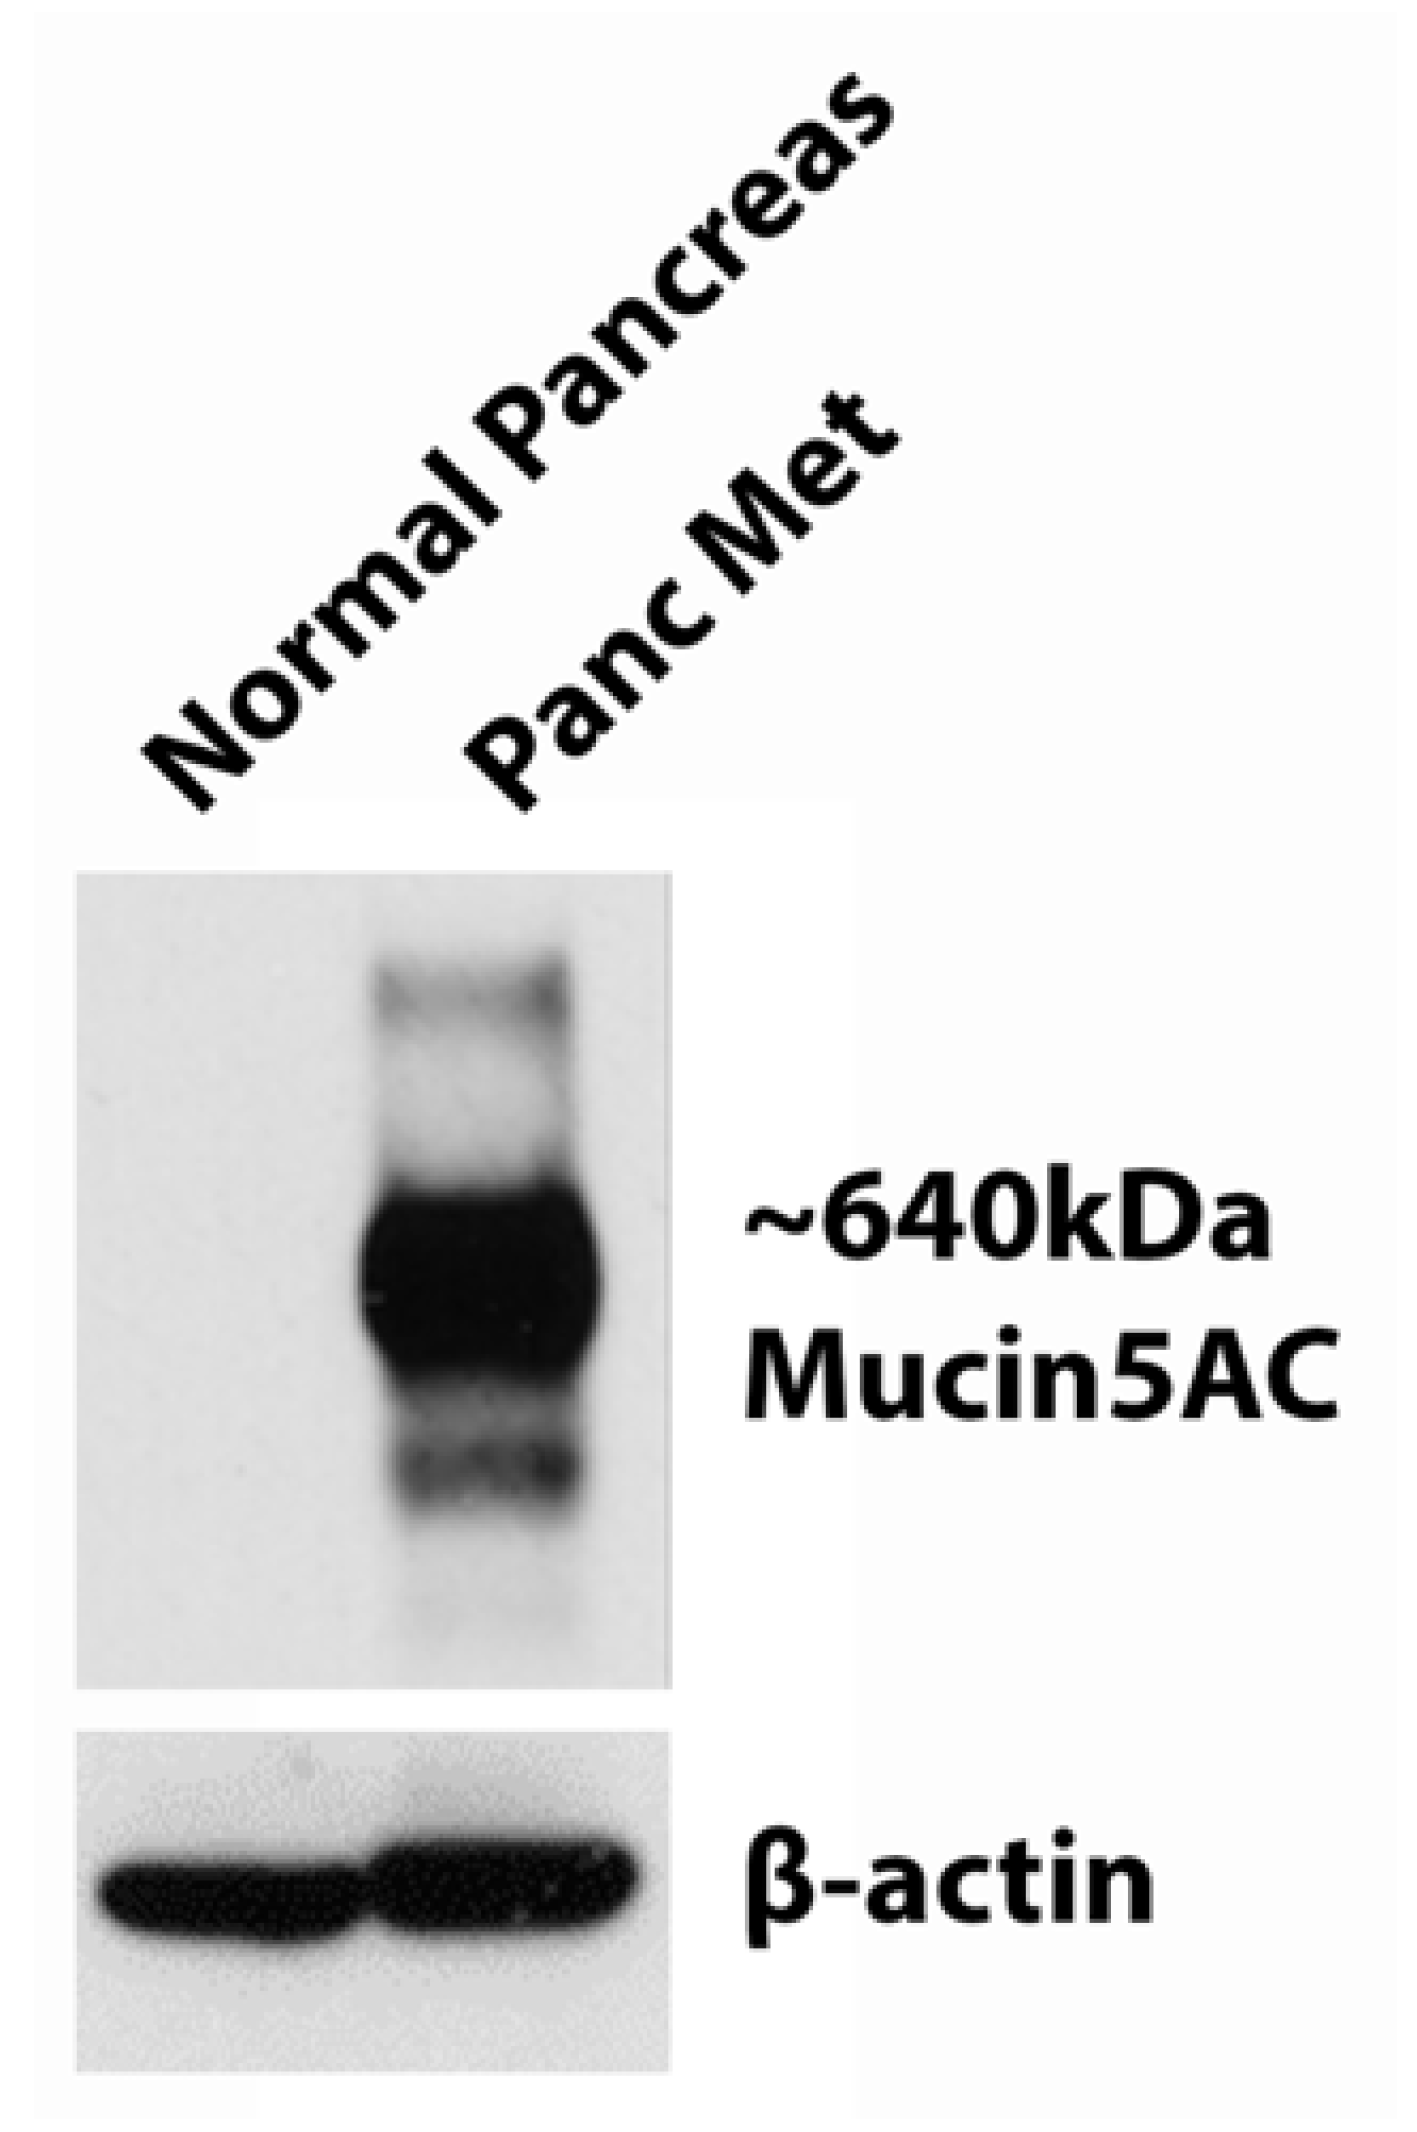

3.2. Western Blot of MUC5AC Expression